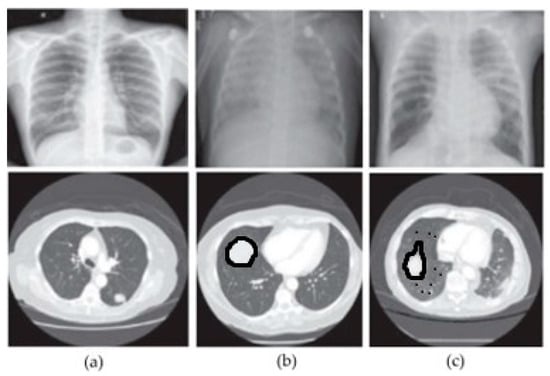

In this section, we show examples from each of the three classes that we used in our study in order to illustrate the variety of images in the dataset. Figure 6 shows a selection of images from both datasets, representing different classes. The first column shows images from the normal class; the second column shows images from the benign class; and the third column shows images from the malignant class. Similarly, the first row represents CXR images corresponding to each class, while the second row represents CT images corresponding to each class.

Figure 6.

Sample images from the adopted datasets. (a) Normal, (b) benign, (c) malignant.

Based on the analysis of Figure 6, we can visually observe a slight similarity between the images indicating a particular pattern. Hence, merging features can improve a machine’s classification accuracy.